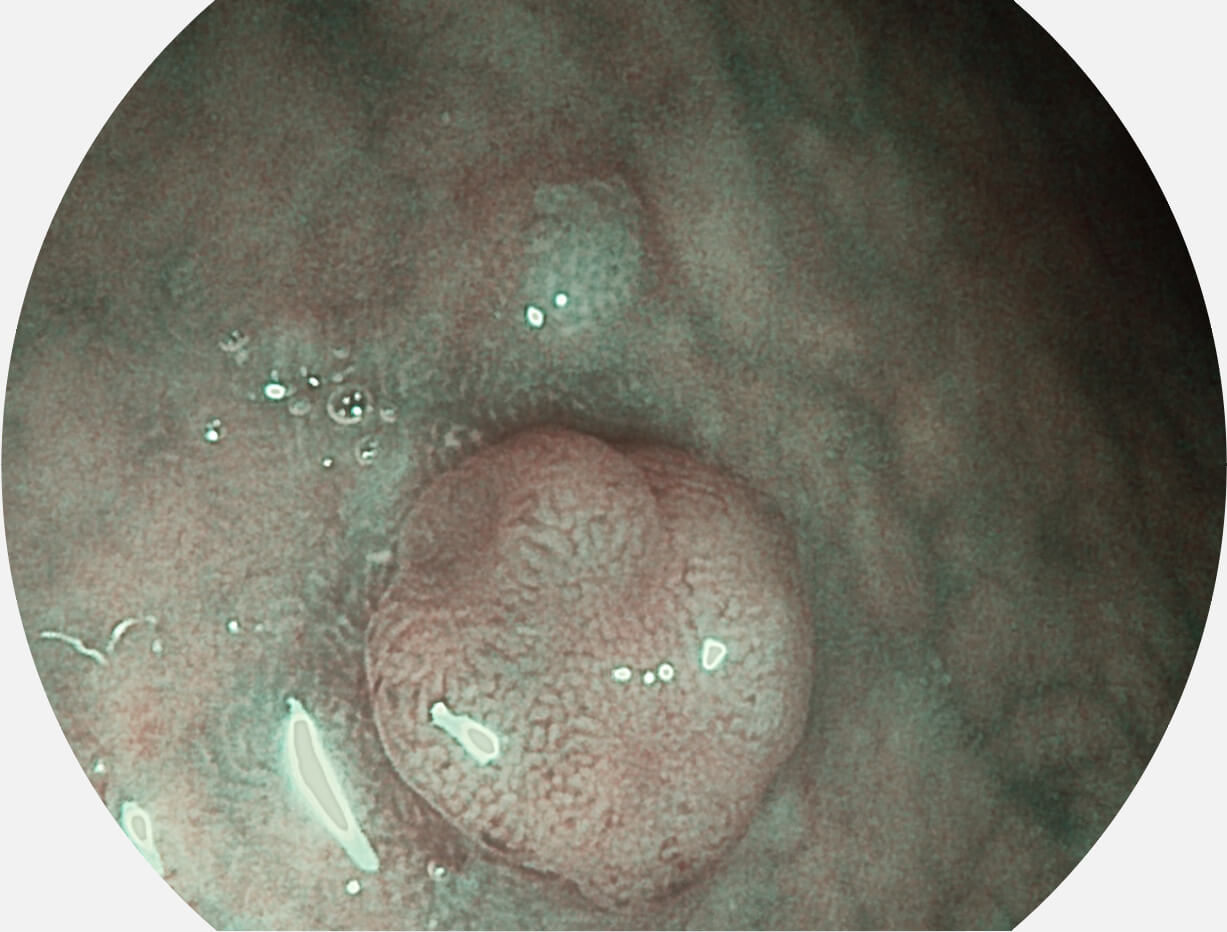

• 白光图像 VIST图像